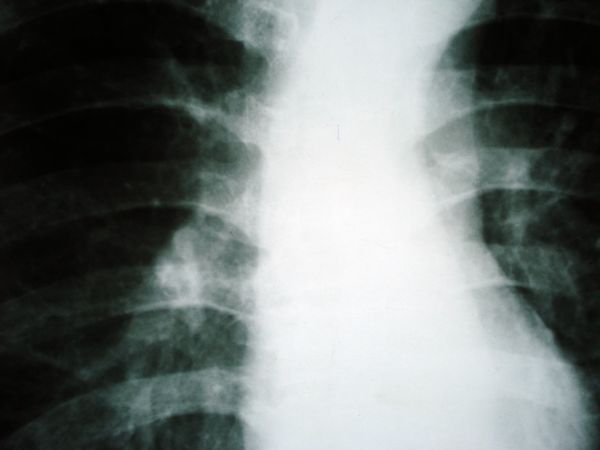

男,54岁,平时有吸烟后咳嗽、咯痰史,因右侧胸部(腋窝下)疼痛来检查平片,见右下肺动脉干起始处处结节,后到同学处做了平扫及增强。请各位老师帮忙看一下,不甚感谢!!!!!

肺窗薄扫、常规扫描均未见明确病变;右下肺门圆形与肺血管等密度影,考虑为血管变异;应该要纵隔窗才能进一步明辨。

x线表现与ct扫描相吻合。